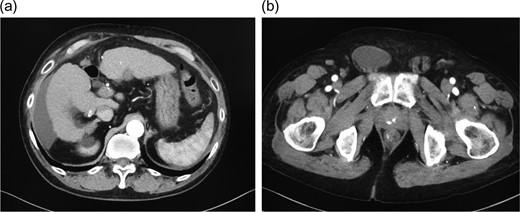

One month before the visit, he noticed swelling in the right inguinal area and mild, palpable swelling on the left area. Abdominal computed tomography revealed the presence of moderate ascites with right inguinal hernia (Fig. 1a and b). He was symptomatic and opted for surgery. Based on preoperative assessments, hernia repair under general anesthesia was considered and TAPP repair was performed.

a) Abdominal contrast-enhanced computed tomography shows moderate ascites in the abdominal cavity. (b) Abdominal contrast-enhanced computed tomography shows an indirect hernia in the right inguinal area, with inflow of ascites into the hernia sac.